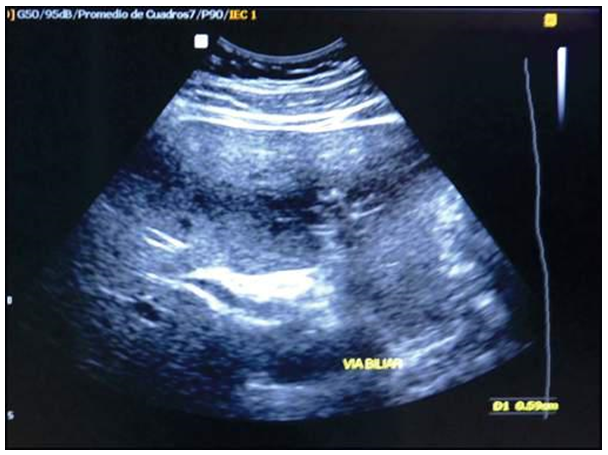

A la exploración física, se encontró estabilidad hemodinámica, semihidratación, anictérico, álgico, abdomen distendido y doloroso a la palpación profunda en epigastrio e hipocondrio derecho con ruidos hidroaéreos disminuidos. Los exámenes de laboratorio al ingreso indicaron leucocitosis (12400/cc), elevación de amilasa a la 3.2 N, lipasa a la 6.8 N, pruebas de función y lesión hepática dentro de parámetros normales, ligera elevación de fosfatasa alcalina y GGT, sin ictericia, PCR de 192 mg/dl y procalcitonina de 0,136 ng/ml (anexos, tabla 1). El ultrasonido de abdomen superior reportó vesícula biliar distendida alitiásica, sin signos dilatación de la vía biliar intra y extra hepática (anexos, figura 1). Se estableció en diagnóstico de pancreatitis aguda alitiásica; la que, de acuerdo con las escalas de gravedad de Ranson, Apache II, BISAP y Marshall modificado, fue de tipo leve.

Hígado de morfología normal, tamaño, ecoestructura normal. Vesícula biliar distendida, sin imágenes litiásicas en su interior. Vías biliares intra y extra hepáticas sin signos de dilatación.